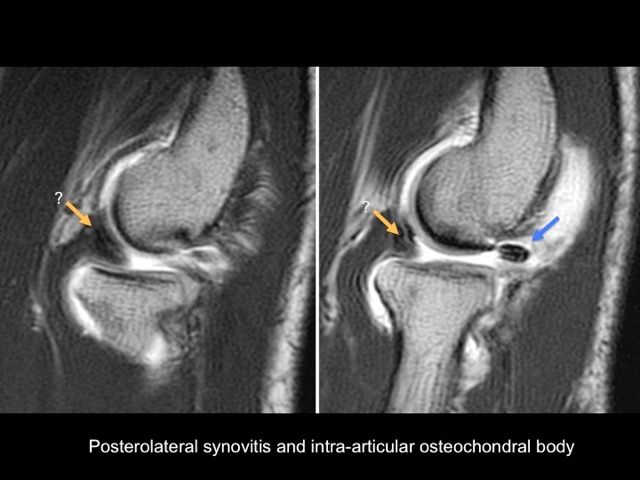

32 year-old-man with posterolateral pain, instability and snapping elbow

Posterolateral elbow instability with intra-articular annular ligament luxation. Associated focal posterolateral synovitis and intra-articular loose body. Reference article.